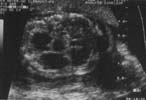

L'échographie met en évidence une masse intra-thoracique [7] :

Le doppler couleur ne retrouve pas de flux à l'intérieur de ces kystes. Il ne retrouve pas non plus de vascularisation aberrante provenant directement de l'aorte.